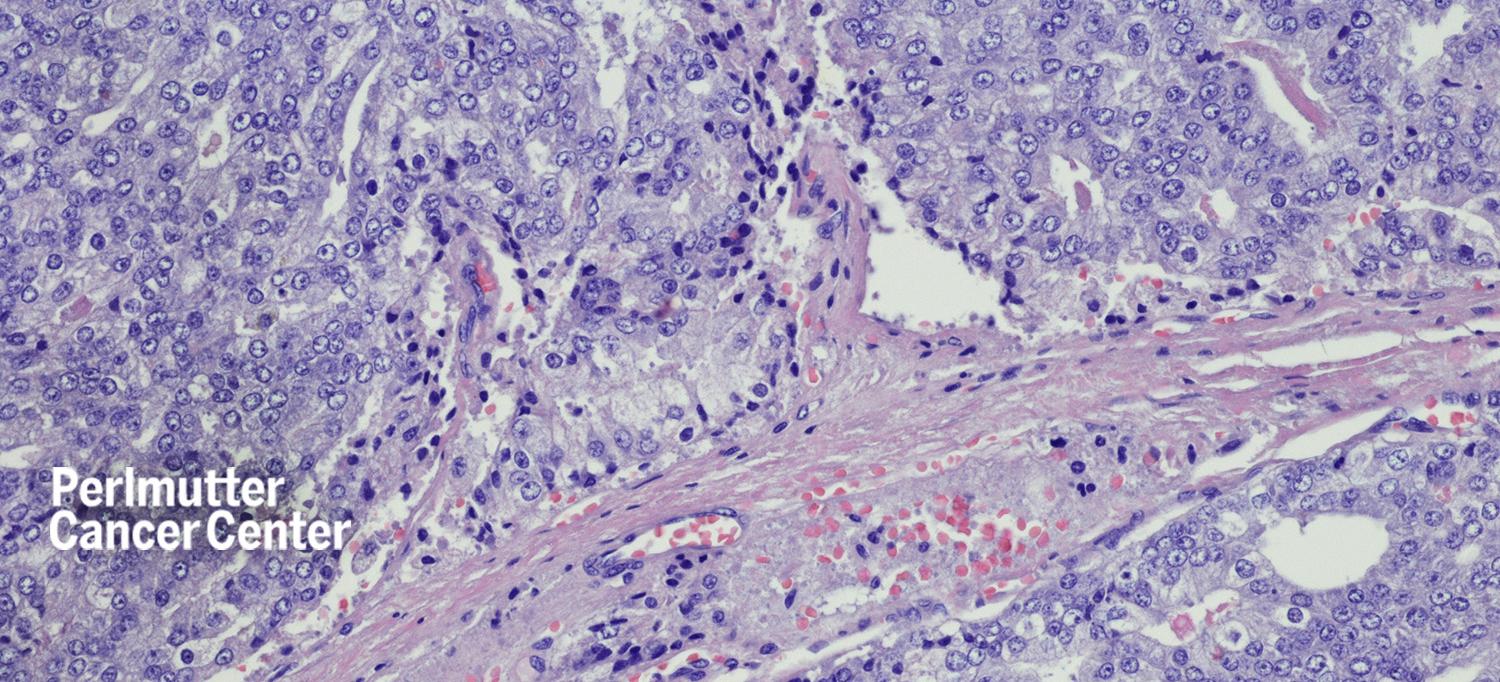

Metastatic, or late-stage, prostate cancer can occur if the cancer spreads to other parts of the body after treatment as well as in people who are not aware they have cancer until it has spread. New advances in treatment are providing new options for people with metastatic prostate cancer. Mary K. O’Keeffe, MD, clinical assistant professor in the Department of Medicine at NYU Long Island School of Medicine and medical oncologist at NYU Langone Health’s Perlmutter Cancer Center, discusses currently available treatments with SurvivorNet. These treatments include PARP inhibitors, which kill cancer cells by targeting a DNA repair protein, and androgen deprivation therapy, which decreases the hormone testosterone.